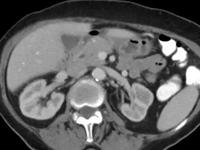

相关图片